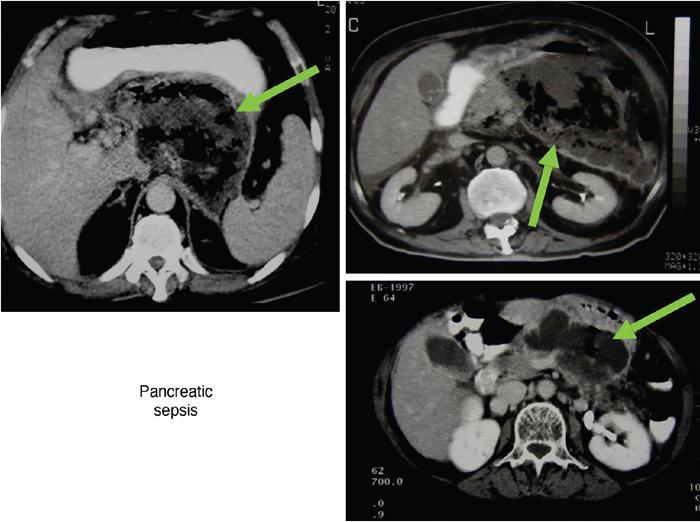

Anirudh Kohli Acute pancreatitis is one of the most dreaded diseases to afflict mankind, in view of its high morbidity and mortality. The single most important factor in reducing the morbidity and mortality of this condition over the last many years has been the role of computed tomography (CT). The incidence of acute pancreatitis is rising especially due to an increasing incidence of gallstones, obesity, as well as an ageing population. Pancreatitis occurs due to a chain of events triggered by a temporary/permanent pancreatic duct obstruction. This leads to activation and release of pancreatic enzymes into pancreatic interstitium and peripancreatic tissues leading to severe auto digestion and necrosis of pancreas and adjacent tissues. Systemically there is release of inflammatory mediators known as cytokines. Tumour necrosis factor is a cytokine which is toxic to acinar cells. These cytokines activate and intensify the inflammatory cascade that may ultimately culminate in multiorgan failure. Clinically severe acute pancreatitis is characterized by two phases, an early phase and a late phase. The early phase is dominated by the systemic effects of release of inflammatory mediators such as cytokines – termed as systemic inflammatory response syndrome (SIRS). Usually there is associated variable multiorgan dysfunction/failure. This phase lasts for a week. When the multiorgan failure lasts 2 days it is termed as mild, multiorgan failure lasting more than 48 hours is considered severe. There is no correlation between the clinical severity of pancreatitis and morphological changes in this early stage. In view of this CT scan is not of much utility during this phase, unless complications are suspected. The later phase is dominated by effects of local complications due to pancreatic/peripancreatic necrosis. Mortality follows this biphasic pattern in early weeks from the systemic effects of multiorgan failure and in later weeks due to local effects, for example infection of necrotic pancreatic/peripancreatic tissues superimposed by organ failure. The Clinical diagnosis of acute pancreatitis requires two of the following three features: If the first two findings are present without any significant SIRS then CT is not required. Acute pancreatitis is a complex disease with a wide variation in the presentation and outcome, ranging from asymptomatic with only biochemical alterations to a fatal outcome. In fact acute pancreatitis is a dynamic disease with continuously evolving appearances on imaging. There are two distinct forms of acute pancreatitis – interstitial oedematous pancreatitis and acute necrotising pancreatitis. Interstitial oedematous pancreatitis is a condition where there is only mild swelling of the pancreas with loss of normal lobulations and a diffuse decrease in attenuation of the pancreas. There may be heterogeneity of the pancreatic parenchyma due to varying degrees of interstitial oedema. This form of pancreatitis runs a mild course and rarely progresses to acute necrotising pancreatitis with its associated complications. In a third of these cases the pancreas may reveal no abnormality on a CT scan. The inflammatory changes may be restricted to the pancreas or extend into the peripancreatic regions. The inflammation in the peripancreatic regions manifests as acute pancreatic effusions. If there is peripancreatic fat necrosis with an oedematous pancreatic gland it is termed as acute necrotising pancreatitis (Figs. 9.17.1–9.17.2). Acute pancreatic fluid collections are enzyme-rich pancreatic juice collections seen in about 40% of patients with acute pancreatitis. The fluid collections occur due to exudation of pancreatic juices into the interstitium of the pancreas and subsequently leakage into the surrounding tissue spaces. These fluid collections are localized only by the anatomic space in which they collect. As the exudative process continues, the parietal peritoneum overlying the pancreas may be disrupted with the inflammatory fluid entering the lesser sac. From the lesser sac the fluid can enter the peritoneal cavity via the foramen of Winslow or by dissecting the peritoneum along the anterior surface of the lesser sac. Posterior extension of the fluid collection in the anterior pararenal space may occur into a potential space between the laminae of the posterior pararenal fascia. Rarely there may be involvement of the perirenal and posterior pararenal spaces. Other pathways of dissection are along the gastrohepatic, gastrosplenic and gastrocolic ligaments. Fluid may dissect along the root of the mesentery into the transverse mesocolon. Collections may extend around the caecum, ascending colon, descending colon and into the lumbar, pelvic and inguinal regions. Large fluid collections may dissect superiorly into the mediastinum or pericardial space. The quantity of fluid in these effusions is variable and can range from a small amount to large quantities (Fig. 9.17.3). Of these collections, 50% resolve spontaneously; the remainder may evolve after 4–6 weeks into pseudocysts. As the collections age, they tend to get localized and walled off, often developing an enhancing wall. A collection should be termed a pseudocyst only when a definite capsule develops and the collection has been static for at least 4–6 weeks. The risk of complications such as rupture, infection and haemorrhage increases with the age of the collection. Large collections of fluid are usually associated with a lesser degree of pancreatic necrosis as compared to extensive pancreatic necrosis associated with a lesser amount of fluid collection. Acute necrotising pancreatitis is a fulminant form of pancreatitis in which there is necrosis of the pancreas, that is nonviable pancreatic tissue. A contrast-enhanced CT is essential as it is the ideal means to demonstrate necrosis as well as to determine the extent of necrosis. These areas of nonviable pancreatic tissue do not enhance as compared to viable pancreatic tissue, which demonstrate significant enhancement. The extent of pancreatic necrosis has been found to correlate extremely well with the extent of necrosis found at surgery. The size, location and extent of pancreatic necrosis are very variable. These areas may be diffuse or focal, small in size to complete glandular involvement. These necrotic areas have a very important bearing on the course of pancreatitis, as they are liable to undergo secondary infection and form pancreatic sepsis. In addition, the more extensive the pancreatic necrosis the greater is the morbidity and mortality. Patients with no pancreatic necrosis have been found to have a 0% mortality and a 6% complication rate, whereas patients with pancreatic necrosis have a 23% mortality rate and an 82% complication rate. A variety of laboratory tests are available to detect pancreatic necrosis, such as a rise in the serum methemalbumin, quantitative estimation of C-reactive protein and urinary trypsinogen-activated peptide. CECT is still the most accurate modality to detect pancreatic necrosis. Pancreatic necrosis may be seen in the pancreas only, peripancreatic tissues also or only in the peripancreatic region. Isolated peripancreatic necrosis occurs due to disruption of the peripheral ductules with extravasation of activated pancreatic enzymes, may be seen in up to 20% of patients who require operative/interventional management of their necrotising pancreatitis. These patients with only peripancreatic necrosis have a better prognosis. This essentially represents retroperitoneal fatty tissue necrosis appearing as heterogeneous areas of liquid and nonliquid components. Over time necrosis evolves and liquefies as well as the liquid component resorbs. Generally if the liquid component is 2 cm or less it will resorb, while fluid collections 5 cm or more rarely resorb. If pancreatic necrosis is not resorbed it may get walled off or with time or may become infected. Encapsulation occurs between the third and fourth weeks. It is important to differentiate sterile from infected necrosis as sterile necrosis rarely needs surgery, whereas infected necrosis requires long-term antibiotic therapy and/or some kind of imaging/surgical intervention. According to the Atlanta 2012 classification, all areas of pancreatic necrosis are termed as acute necrotic collections. This represents a combination of pancreatic/peripancreatic fat necrosis with peripancreatic effusions. On CT, there is a spectrum of findings – solid, liquid containing debris (these may be nonwalled off/partially walled off). Sonography and MRI have advantages over CT scan in demonstration if the contents are pure liquid such as acute pancreatic effusions or have some nonliquefied components such as acute necrotic collections. Pseudocysts are round or oval encapsulated fluid collections containing only liquefied components. It takes 4 weeks for the granulation tissue to develop. On CT, a pseudocyst appears as a well-defined fluid collection with a thin capsule. The most common location for pseudocysts is the lesser sac, though they may be found anywhere in the mediastinum, abdomen or pelvis as they may dissect along fascial planes, along vessels and through capsules of solid organs. Pseudocysts in the bowel, though reported, are relatively rare, as the bowel wall is a strong barrier to the effect of proteolytic pancreatic enzymes. When the contents of the pseudocyst are heterogeneous or uniformly increased in attenuation, the possibilities of infection or haemorrhage should be considered. Focal areas of increased density within the fluid collection usually indicate haemorrhage. Complicated, enlarging or symptomatic pseudocysts require percutaneous catheter or surgical drainage. Infected pseudocysts are treated by percutaneous drainage. The management of a noninfected pseudocyst is controversial. Surgical treatment is only undertaken when the wall is mature after several weeks. Large pseudocysts greater than 5 cm in size can easily be drained percutaneously using intercostal drainage tube or pigtail catheter or endoscopically via the stomach. The cure rates are reported to be 85% with percutaneous drainage, the drainage period averaging about 20 days (Figs. 9.17.4–9.17.5). Walled off necrosis – as pancreatic/peripancreatic necrosis matures and evolves, an interface develops between necrosis and adjacent fatty tissue and an enhancing thickened wall is seen, resulting in a well-defined fluid collection with necrotic debris and fat necrosis. This is the end stage in the evolution of an acute necrotic collection. It is important to differentiate a pseudocyst from walled off necrosis, as a pseudocyst requires drainage and walled off necrosis requires surgical removal (Figs. 9.17.6–9.17.9). Sepsis is a major complication of pancreatitis and is accompanied by a high incidence of mortality and a prolonged hospital stay. Pancreatic sepsis may occur following secondary infection of pancreatic and/or peripancreatic necrosis, acute pancreatic fluid collections and pseudocysts. The only specific sign to demonstrate sepsis is the presence of gas in a collection. This occurs due to secondary infection by coliform/anaerobic organisms. This sign is unfortunately not common and seen in only one-third of cases. Gas is seen in the fluid collection as very dark well-defined air attenuation bubbles. Occasionally gas may be present due to a gastrointestinal fistula or previous surgery. Fat necrosis is seen in peripancreatic collections. This should not be confused with air bubbles, which are indicative of sepsis. The differentiation is easy to understand by CT, the values of fat ranging between – 20 HU and – 80 HU, and of air being >–300 HU. Also air bubbles have well-defined margins and are homogeneously jet black, whereas fat is nonhomogeneously grey with ill-defined margins. Since the presence of air is seen only in a small percentage of patients with pancreatic sepsis, the only other means to diagnose pancreatic sepsis is by CT-guided aspiration. All sites of fluid collection, parenchymal necrosis and peripancreatic necrosis are subjected to CT-guided aspiration. This is a tedious process and requires a dedicated interventional radiologist as there are often more than 5–6 sites from which it may be necessary to obtain samples. A fresh needle and syringe are used for each site, as it is important to know which site has sepsis and which is sterile. Care is taken not to transgress the large bowel as the colon has a large number of bacteria, and transgressing it could result in colonic bacteria contaminating the CT-guided aspiration sample, with falsepositive results. Further, colonic bacteria may be inoculated into a sterile acute pancreatic fluid collection or necrosis thereby converting a sterile collection into an infected one (Fig. 9.17.10). Complications of the procedure can be pneumothorax if the pleura is transgressed, haemorrhage due to trauma to a vessel, and secondary infection. Pancreatic sepsis is treated by surgical debridement, necrosectomy and drainage through thick tubes. It is crucial from the management point of view to differentiate an abscess from infected necrosis. An abscess may be treated by percutaneous drainage, whereas infected necrosis developing in relatively solid tissue can be treated by surgical debridement alone. Imaging-guided percutaneous drainage is the first step in treating pancreatic sepsis especially patients who are very ill and cannot undergo surgery. Initially pig tail catheters were used but these are notorious to get blocked as the largest bore of a pigtail catheter is 12 F. Pancreatic sepsis contains a large amount of necrotic debris, this blocks the catheters can be cleared by flushing the catheter, but this always raises the possibility of introducing secondary infection. To circumvent this issue large-bore ICD catheters have been introduced. These range from 16 F to 30 F. A safe window is necessary, not transgressing bowel or vasculature. It is quite easy to insert these tubes percutaneously under CT. A bit of initial manipulation and force is required to pierce the abdominal musculature. These large-bore drainage tubes have been very effective unless the infected necrosis is solid with minimal liquefied contents or a safe window for placing an ICD catheter is not available. CT is also invaluable in surgical planning and in the follow-up of postoperative patients to evaluate any fresh collection and also to determine whether the drains are well sited or not (Fig. 9.17.11).